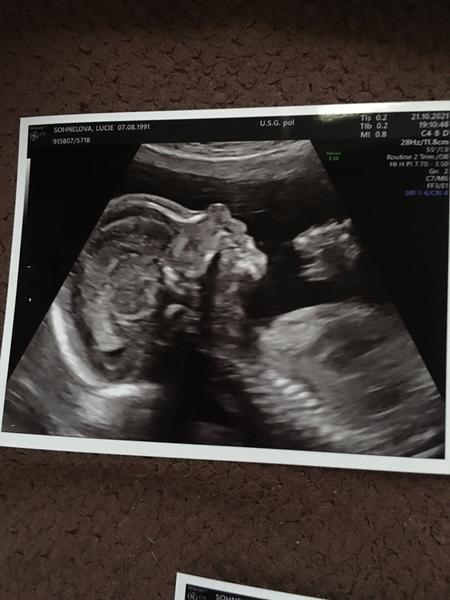

Ahojky, tak se hlásím po dlouhé době. Dnes 26+1 jsem byla na testech na těhotenskou cukrovku a dalo se to v klidu zvládnout ( zítra výsledky ... snad bude vše v pořádku). V 1 trimestru mne zlobil hematom, ve druhém pro změnu polyp, ale už to beru jako samozřejmost 🙂. Čekáme chlapečka. Už ho pěkně cítím já i manžel, i když mám placentu uloženou na přední straně. Asi dva dny zpět mne začala pálit žáha na kterou mi naštěstí zabírá Rennie. Výbavička se mi pomalu ale jistě kupí na balkóně ... už jen postýlka a vymalování ložnice chybí 🙂 🙂

@snazilka3 ahoj, to je paráda 😊 ja jsem dnes 23+0 a v 18tt jsem byla na plodovce, kde vyšlo naštěstí vsehcno v pořádku jen ma maly vadu jako já.. Je přenašeč a ma balancovanou aberaci... Asi týden po plodovce jsem byla v nemocnici, protože mam problémy s pupikem, které jsem měla už dříve, takže teď je to mnohem horší, jak všechno roste a roztahuje se, takže někdy umíram bolesti.. Musím si stále dávat pozor na každý pohyb, nesmím zatinat břicho, dělat prudké pohyby, předklanet se, a příště se pupiku nesmím ani dotknout, jinak mi to hned začne.. Nevím, co to jena ani doktoři.. Pry může být něco v břiše, jako třeba srusty nebo tak něco.. Takže nemůžu ani ns procházku, protože jdu kousek a uz to bolí, jsem z toho špatná, chteka jsem být v těhotenství aktivní a nemůžu. Takže mam strach z každého dne, jak mi poroste bříško, tak to bude určitě horší a horší, jenže když mi to začne, tak se ta bolest nedá vydržet ale prý se nic jiného dělat nedá.. Takže ani nevím, jak porodim, když nemůžu ani na wc tlačit.. Jinak jsou i jiné problémy 🤣 pálení záhy, hemeroidy, bolest zad a kyčli, bolavé a krvácení dásní, 7 kilo nahoře, velká a bolavá prsa.. Std atd.. Bych tu byla do zítra.. Takže sice jsem šťastná, ze čekám nase vymodlene miminko ale těhotenství si opravdu neužívám, uz se těším, až tu bude konecne s námi 😊😊 také čekám chlapečka a placenta vepředu a pohyby od 18tt..od 20tt pravidelně a cítí i přítel, kope jako blázen, ze se hýbe celé břicho a večer me nenechá spát, takže se opravdu někdy nevyspim.. No jsem zvědavá, co bude dál 😀😀. Vybavicku také pomalu a jistě chystám.. Nejprve se chystá pokojíček ale plno věcí už mám... Tak hodně štěstí 🍀

Ahoj, ja začínám 34tt a čekáme chlapečka 💙... Otěhotněla jsem v červenci z druhého KET... Poslední kontorla ve 32+5a maly ma pry moc velké bříško, mam vynechat sladké. Mam o nej strach ale jinak by mělo byt všechno v pořádku. Termín mám 9.4 a uz bych ráda, aby to bylo 😀